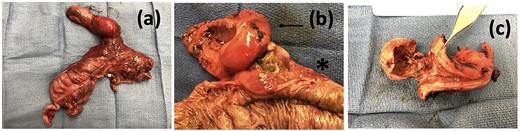

Operative specimen showing the gallbladder and colon resected in bloc (a) En-bloc specimen (b) Gallbladder (arrow) tightly adherent to colon (start) and (c) macroscopic appearance of the cholecystocolonic fistula.

Case presentation #2: A 39-year-old male initially presented with acute cholecystitis (AC) with a markedly thickened wall with abscess formation, not amenable for drainage, treated with antibiotics with improvement, but later experienced recurrent biliary colic symptoms. Repeat computed tomography (CT) imaging (Fig. 4) 2 months later showed a peripherally hyperdense septated collection within the porta hepatis with surrounding fluid signal attenuation; likely representing an abscess seen around the gallbladder possibly secondary to gallbladder perforation due to neoplastic versus inflammatory pathology. Ultrasound showed chronic cholecystitis with cholelithiasis. The patient later underwent elective laparoscopic cholecystectomy. Intraoperatively, extensive adhesions from the liver to the gallbladder and the colon to the gallbladder were noted. The fundus of the gallbladder was densely adherent to the hepatic flexure with no dissection plane. The hepatic flexure felt firm, raising concern of a possible tumor or fistula. The decision was made to remove the right colon en-bloc with the gallbladder. The gallbladder was dissected free in the usual manner and a critical view was obtained. Once the gallbladder was freed, we proceeded with a laparoscopic right hemicolectomy with ileocolonic anastomosis. The specimen was evaluated on the back table; no tumor was seen, but there was what appeared to be an abscess cavity adherent between the gallbladder and colon filled with green stool-colored liquid. The patient tolerated the procedure well and was progressively advanced to regular diet postoperatively and discharged on postoperative Day 3. His final pathology of the operative specimen (Fig. 5) came back as acute on chronic cholecystitis with a micro-fistula between the gallbladder and the adjacent colon.